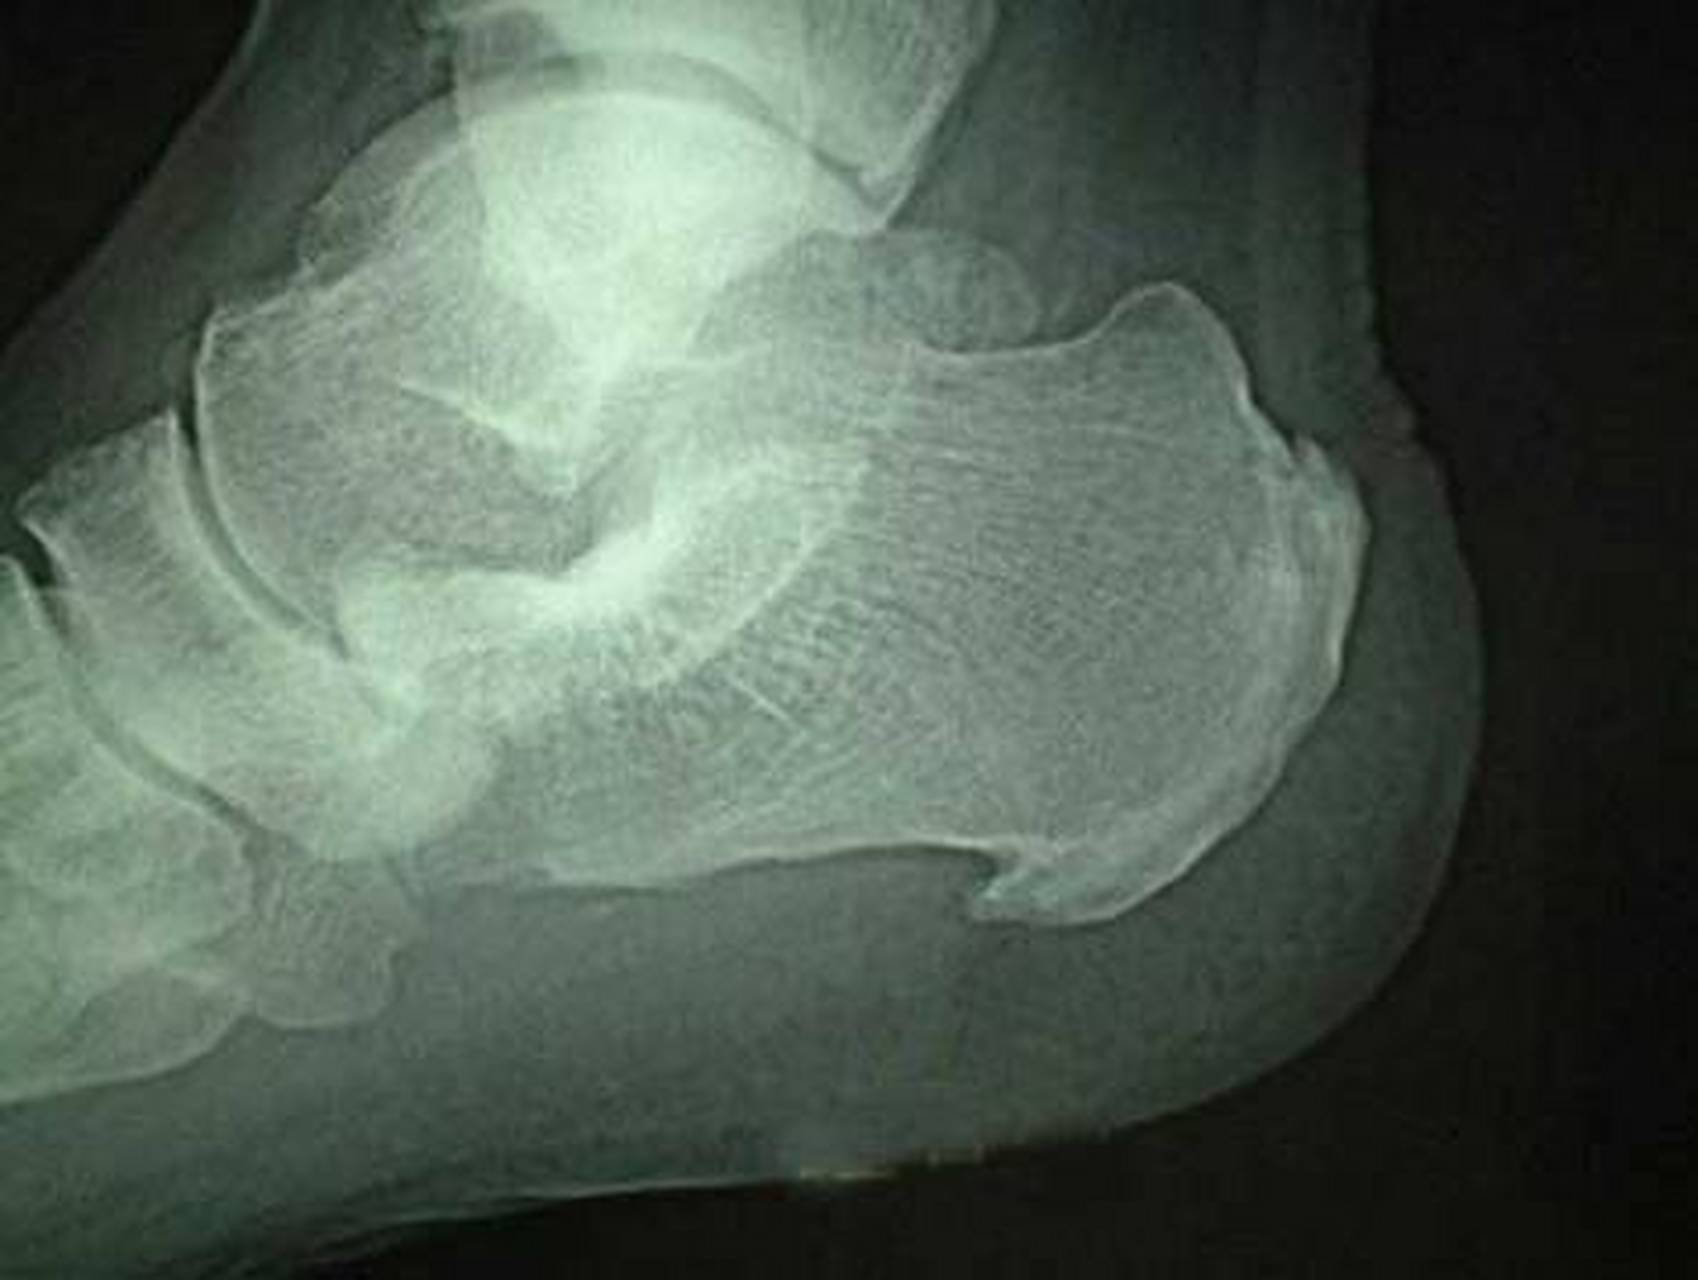

跟骨骨刺

脚跟骨刺的形成多于足跟长时间的负重和磨损有关,当足跟关节出现

足跟骨骨刺怎么治疗?

患者术后足跟部疼痛症状明显缓解,关节镜下切除跟骨骨刺治疗顽固性